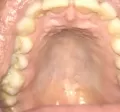

Восемь месяцев назад у меня заболело в области носоглотки. На утро облезло мягкое небо при этом язык был желтого цвета. На другой день с внутренней стороны нижней губы появилась язвочка в виде стоматита. Всё это я самостоятельно залечила неделю, но потом начались мои мучения на протяжении восьми месяцев. То у меня ком в горле, то у меня боль в носоглотке, то опять облазит небо, то сухость в глотке и носу. Теперь ещё ноют зубы, дергается верхняя губа, не приятные ощущения в переносице, в висках, лоб ломит, но не сильно. Иногда даже за ушами болевые ощущения при этом всем чувство толи в трахее толи в корне языка постоянно присутствует боль. Прошла невролога (шейный остеохондроз), МРТ головного мозга (норма), гастроэнтеролога (Эзофагит, назначено лечение, пролечилась), ФГС (гастрит пролечила), щитовидка в норме. Органы брюшной полости по УЗИ норма. ЛОР ничего не увидел, сказал всё идеально, назначил Мирамистин, Фалеминт, витамин А, полоскание солевым раствором (облегчение было, но ненадолго). Вчера с утра сильно заболело горло, пошла снова к ЛОРу ничего не увидел, назначил мазок из зева (готов будет через 5 дней). Вечером выпила обезболивающее, горло перестало болеть. Сегодня с утра заболел язык слева. Посмотрела в зеркало, имеется очень меленький белый прыщик.

• По фото определить характер образования очень сложно. Это может быть участок раздражения (аллергическая реакция, химическое или термическое раздражение, инфекционное поражение). Вам необходимо обратиться к стоматологу-терапевту для проведения клинического осмотра полости рта.